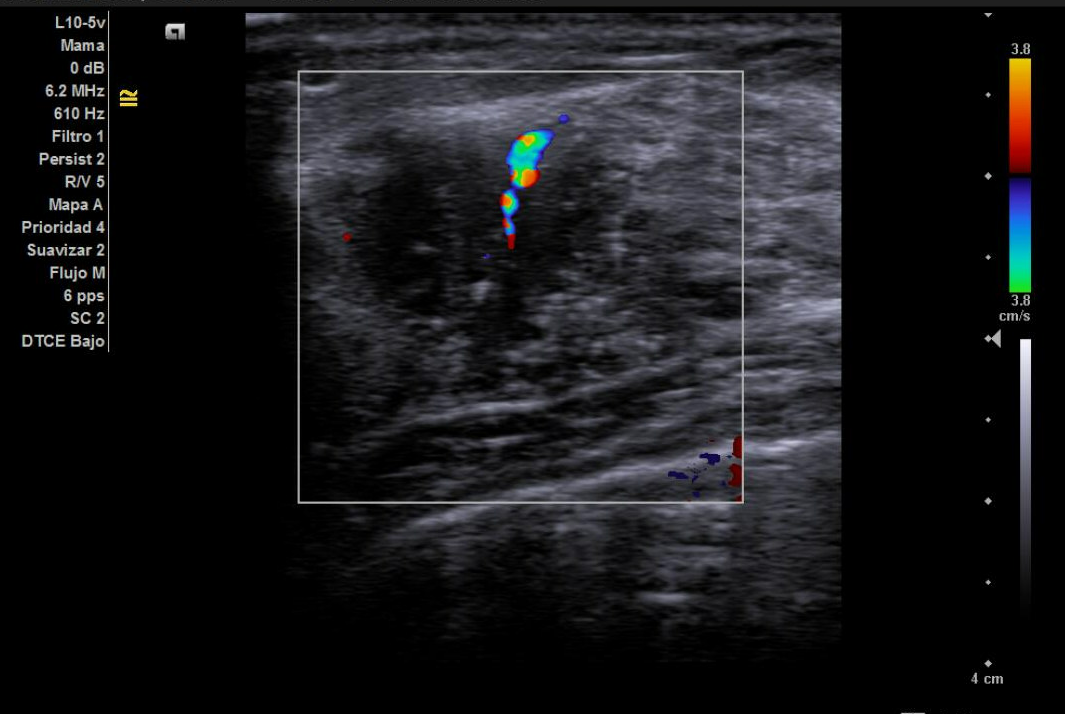

Ecografía no reglada en AP: nódulo de 2,3 cm x 1,4 cm con bordes irregulares no bien delimitados, hipoecoica, heterogénea en donde hay zonas espiculadas, con microcalcificaciones y captación Doppler en interior.